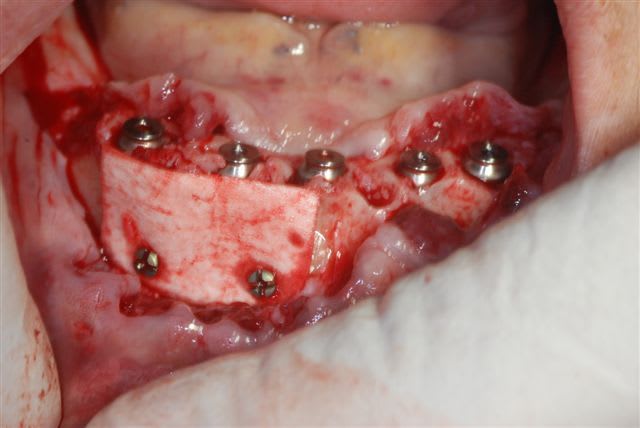

un petit cas clinique de cet après midi:

la pano post op

j'avais prévu de faire une MCI mais le manque de stabilité primaire des 2 implants côté droit m'en a dissuadé.

membrane biomend extend stabilisée par 2 petites vis de 4 mm de long de chez esasy implant. Os autogène et un peu de bio-os mélangé pour combler le defect.